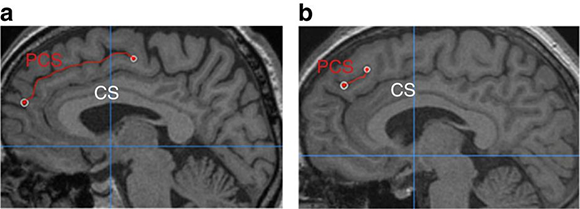

קפל מסוים מופיע רק אצל 60-30 אחוז מהאוכלוסייה, ועשוי להיות במחצית הימנית או השמאלית של המוח, או בשתיהן. הקפל, שנקרא Paracingulate sulcus, מסומן באדום בתמונות | מתוך המאמר Garrison et al., Nature communications 2015

ובכל זאת, לא כל המוחות הם בעלי מבנה זהה. אחד מגורמי השוני הבולטים ביותר הוא שקע מסוים, שמתפתח רק אצל 60-30 אחוזים מהאוכלוסייה. שקע זה, הנקרא בשם Paracingulate sulcus, הוא חלק מאזור הנקרא "פיתול החגורה הקדמי" (Anterior cingulate cortex). קפל מיוחד זה נוצר בשלבים מאוחרים של ההתפתחות ויכול להיווצר גם באופן א-סימטרי, כלומר רק באחת משתי המחציות (ההמיספרות) של המוח. לרוב הוא נמצא במחצית השמאלית.